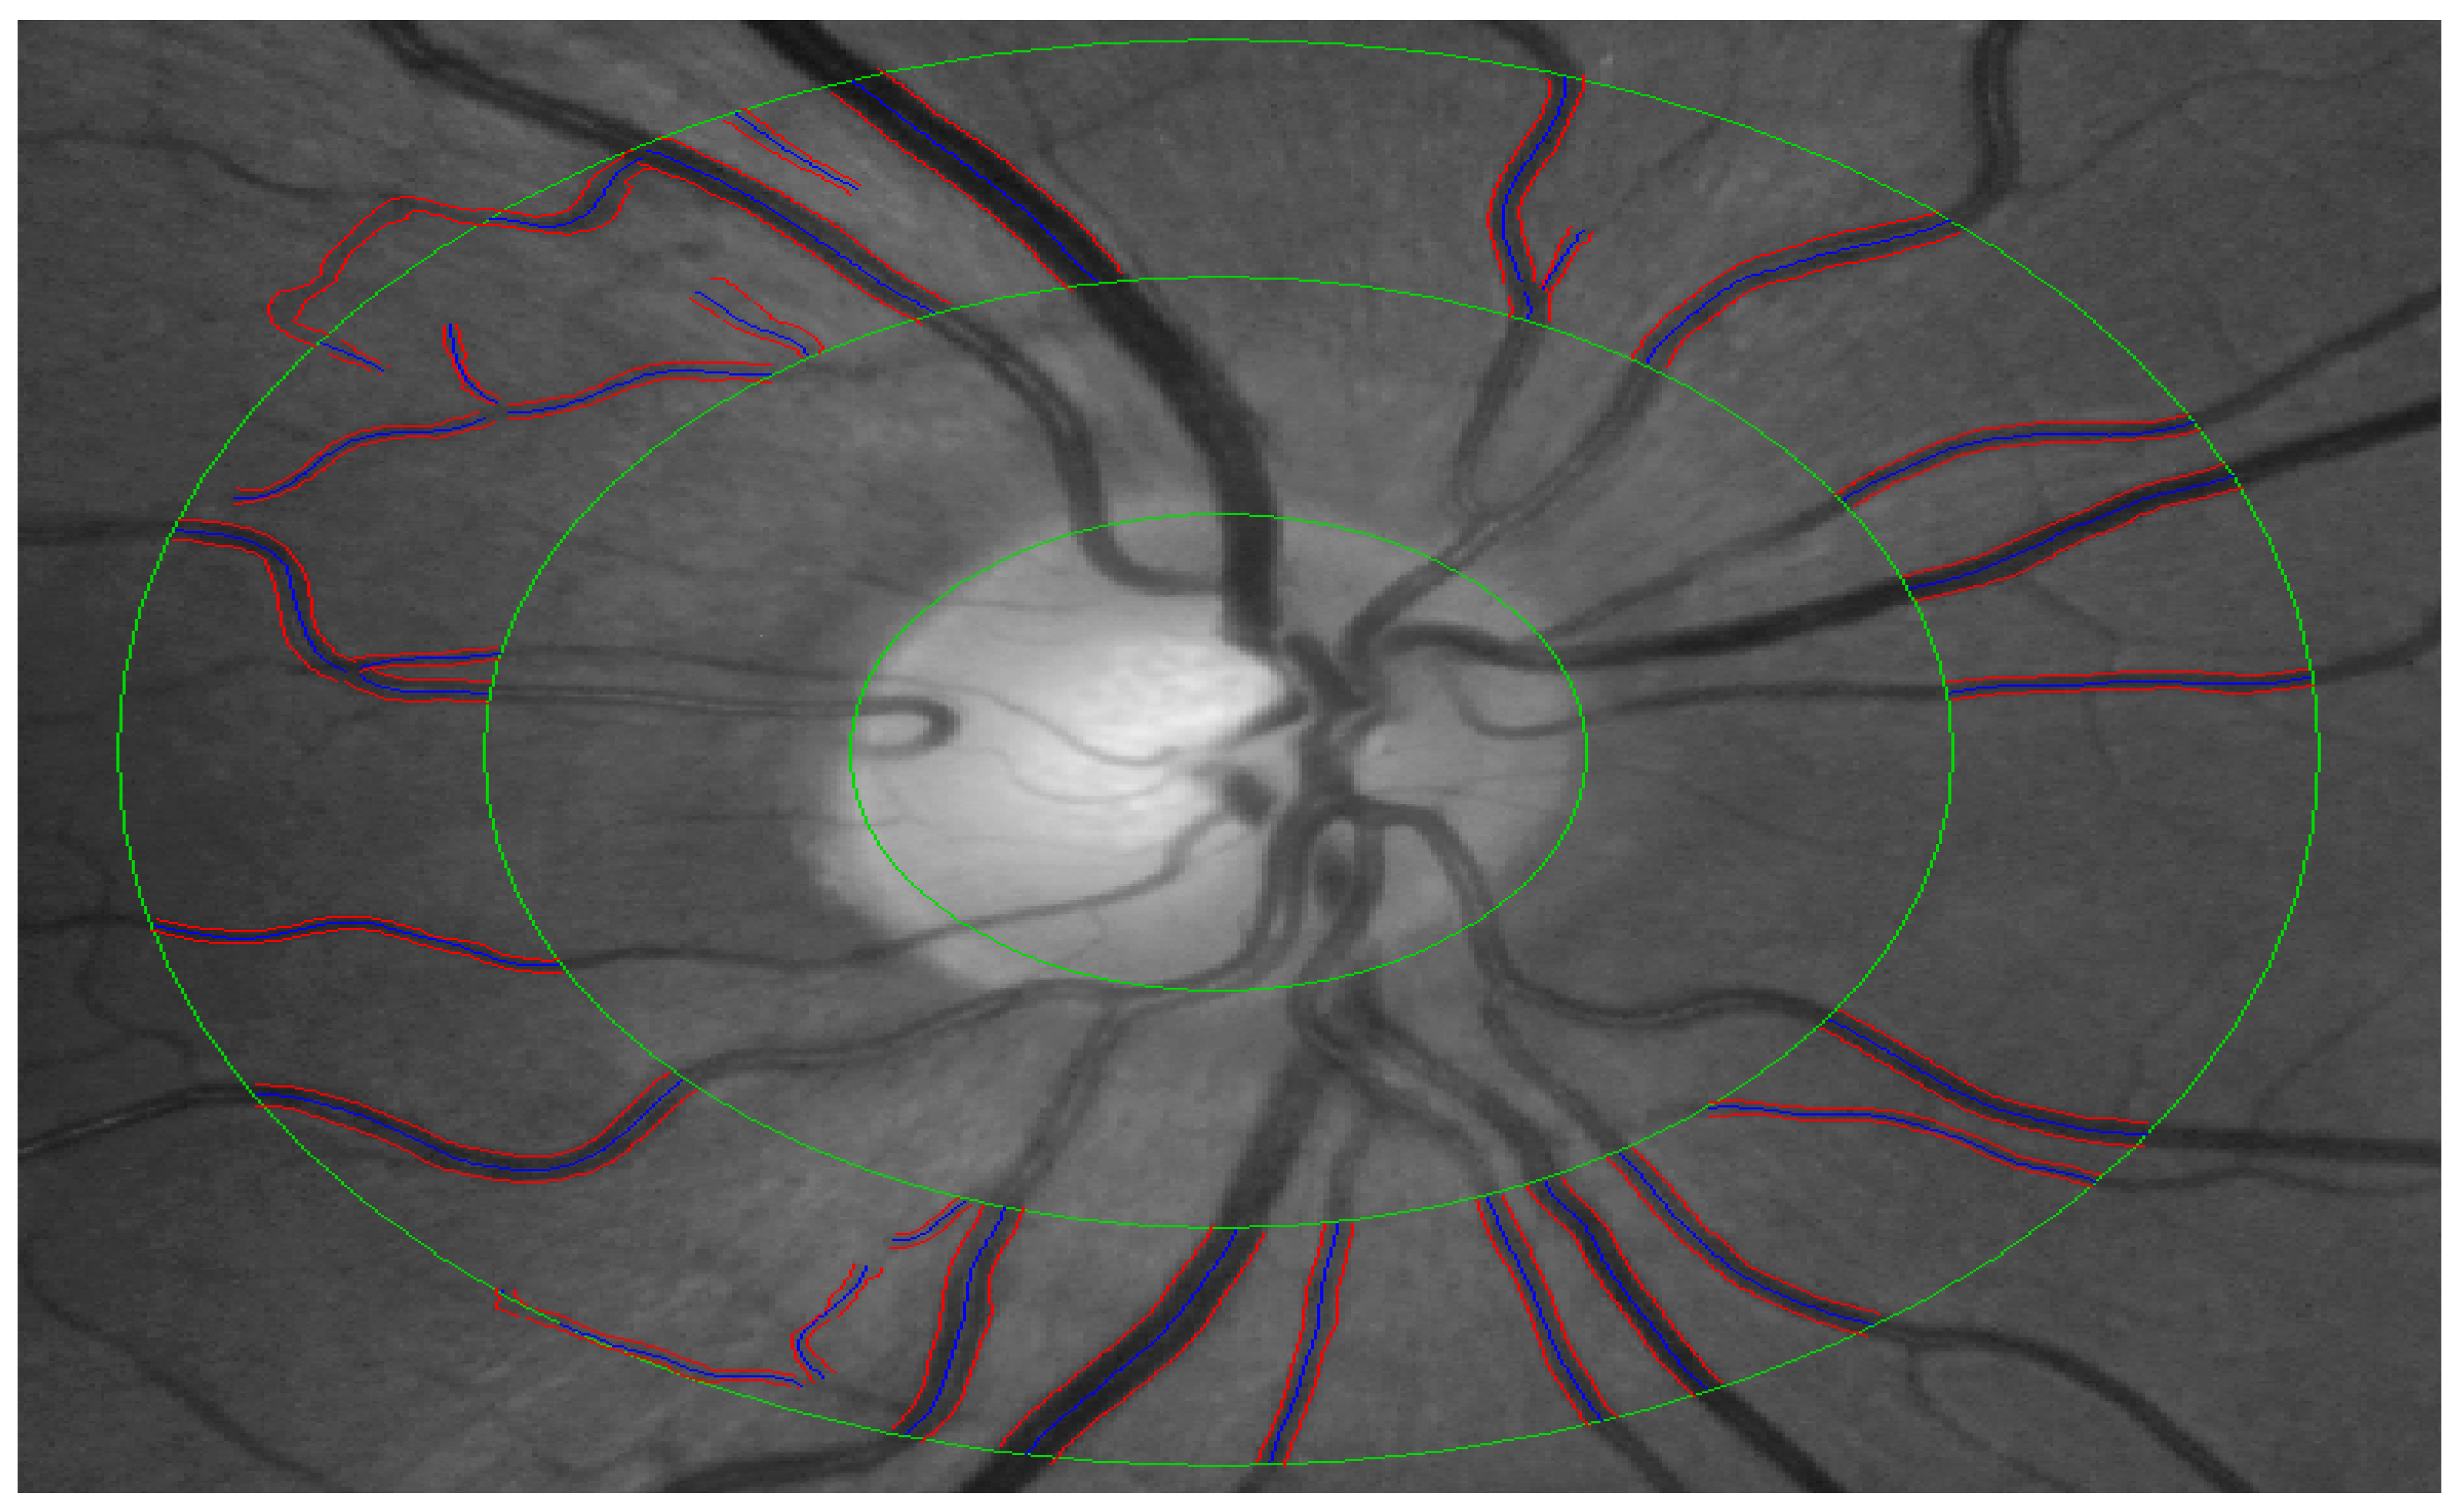

2.5. Quantification of Retinal Vessel Calibre (CRAE, CRVE and AVR)

| CRAE (μm) | 143.70 (13.97) | 149.31 (12.05) | 0.003 * |

| CRVE (μm) | 204.72 (23.26) | 213.24 (20.75) | 0.007 * |

| AVR | 0.67 (0.08) | 0.65 (0.08) | 0.068 |